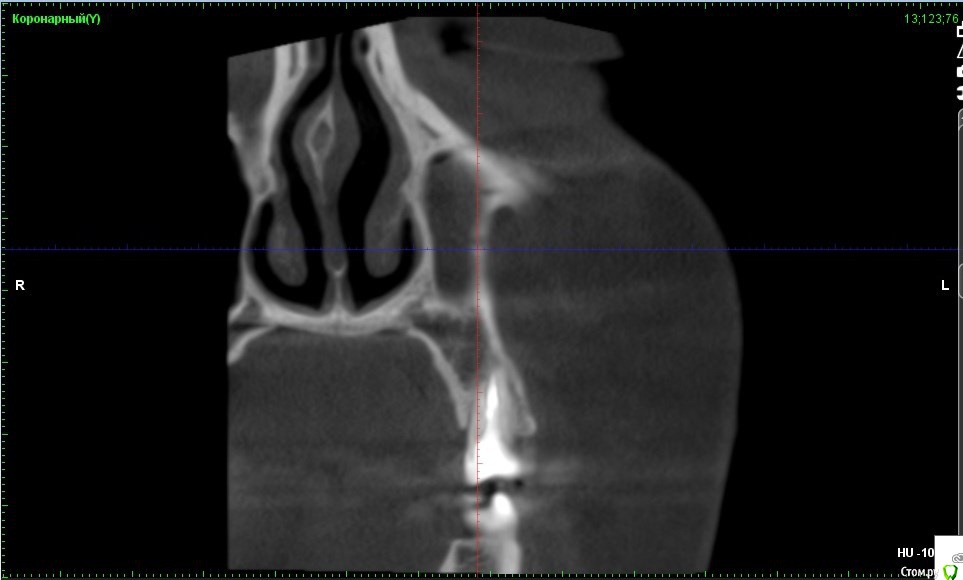

Verasss Опубликовано 8 октября, 2016 Автор Поделиться Опубликовано 8 октября, 2016 КТ от 08.09. Извините, что в таком виде, надо менять ОЗУ. Ссылка на комментарий

DmitrySH Опубликовано 8 октября, 2016 Поделиться Опубликовано 8 октября, 2016 В таком виде КТ малоинформативно. Но гайморита нет. Ссылка на комментарий

Verasss Опубликовано 28 октября, 2016 Автор Поделиться Опубликовано 28 октября, 2016 Добрый вечер! Ещё раз попытаюсь прикрепить скриншоты КТ от сентября. Если качество совсем не устраивает, подскажите, пожалуйста, какие сделать снимки?К сожалению, программа не позволяет вывести снимки на полный экран и заскриншотить в более хорошем качестве. Ссылка на комментарий

Verasss Опубликовано 28 октября, 2016 Автор Поделиться Опубликовано 28 октября, 2016 еще снимки Ссылка на комментарий

Verasss Опубликовано 23 ноября, 2016 Автор Поделиться Опубликовано 23 ноября, 2016 Сделала ещё 1 кт, спустя почти 2,5 месяца после первого. Посмотрите, пожалуйста, есть ли изменения? Напомню, что пункцию гайморовой мне сделали. Ссылка на комментарий